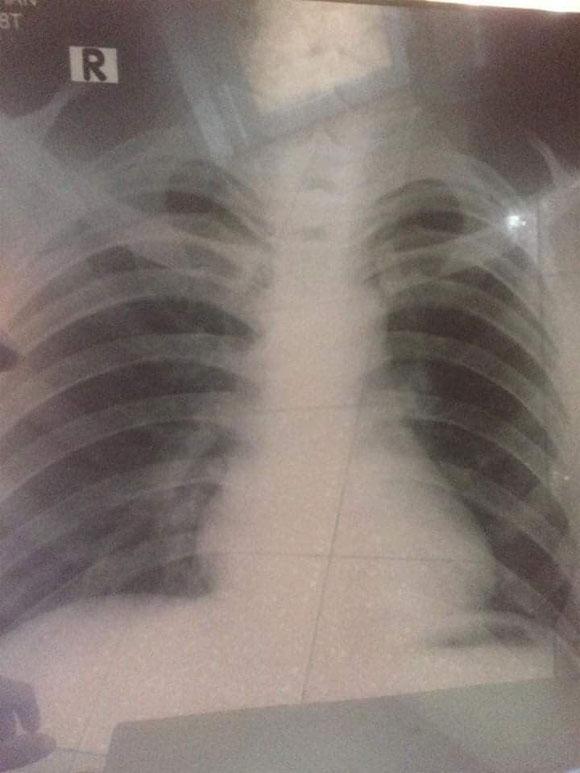

Nhưng mấy hôm nay tôi thấy ngực mình đau nhức quặn từng cơn và số lần đau càng ngày càng tăng không hề giảm. Tôi quyết định đi khám xem sao. Sau khi làm đầy đủ các xét nghiệm và phép thử, bác sĩ bảo tôi đã bị ung thư. Tôi nghe tin, toàn thân, đầu óc không còn được bình thường nữa. Tôi thấy thất vọng lắm. Nước mắt ướt cả khóe mi.

Lần đầu tiên tôi khóc trong vô thức và như kiểu không tự chủ được suy nghĩ. Một thằng con trai duy nhất được gọi là cậu ấm trong gia đình mà án tử đã treo trên cổ. Mới ngày nào tôi còn đang chứng tỏ mình trưởng thành thì giờ đây tôi lại hối hận vì hành động ngu ngốc ấy vô cùng. 20 tuổi đầu với bao hoài bão, dự định tương lai mà nay đã bị chuẩn đoán ung thư phổi giai đoạn 2.

Dù còn trẻ chàng trai đã phải đối diện với căn bệnh ung thư phổi quái ác do hút thuốc từ khi còn sớm.